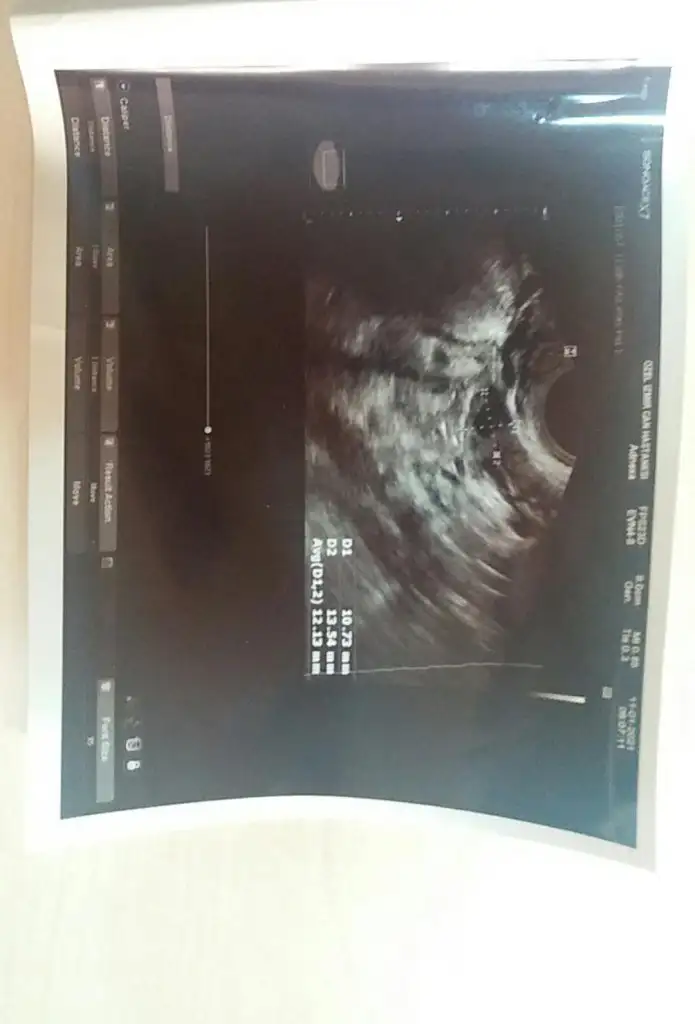

11.01.2021 tarihinde başka hastanede 4815 beta hcg çıktı ve kese gözükmedi doktorum ıkı gun sonra tekrar beta hcg ıstedı sızce dış gebelik mi geç döllenme olabılırmı?aşağıda ultroson goruntulerını paylaştım doktorum rahım kalınlıgımın cok ıyı oldugunu soyledı.Yardımcı olurmusunuz.